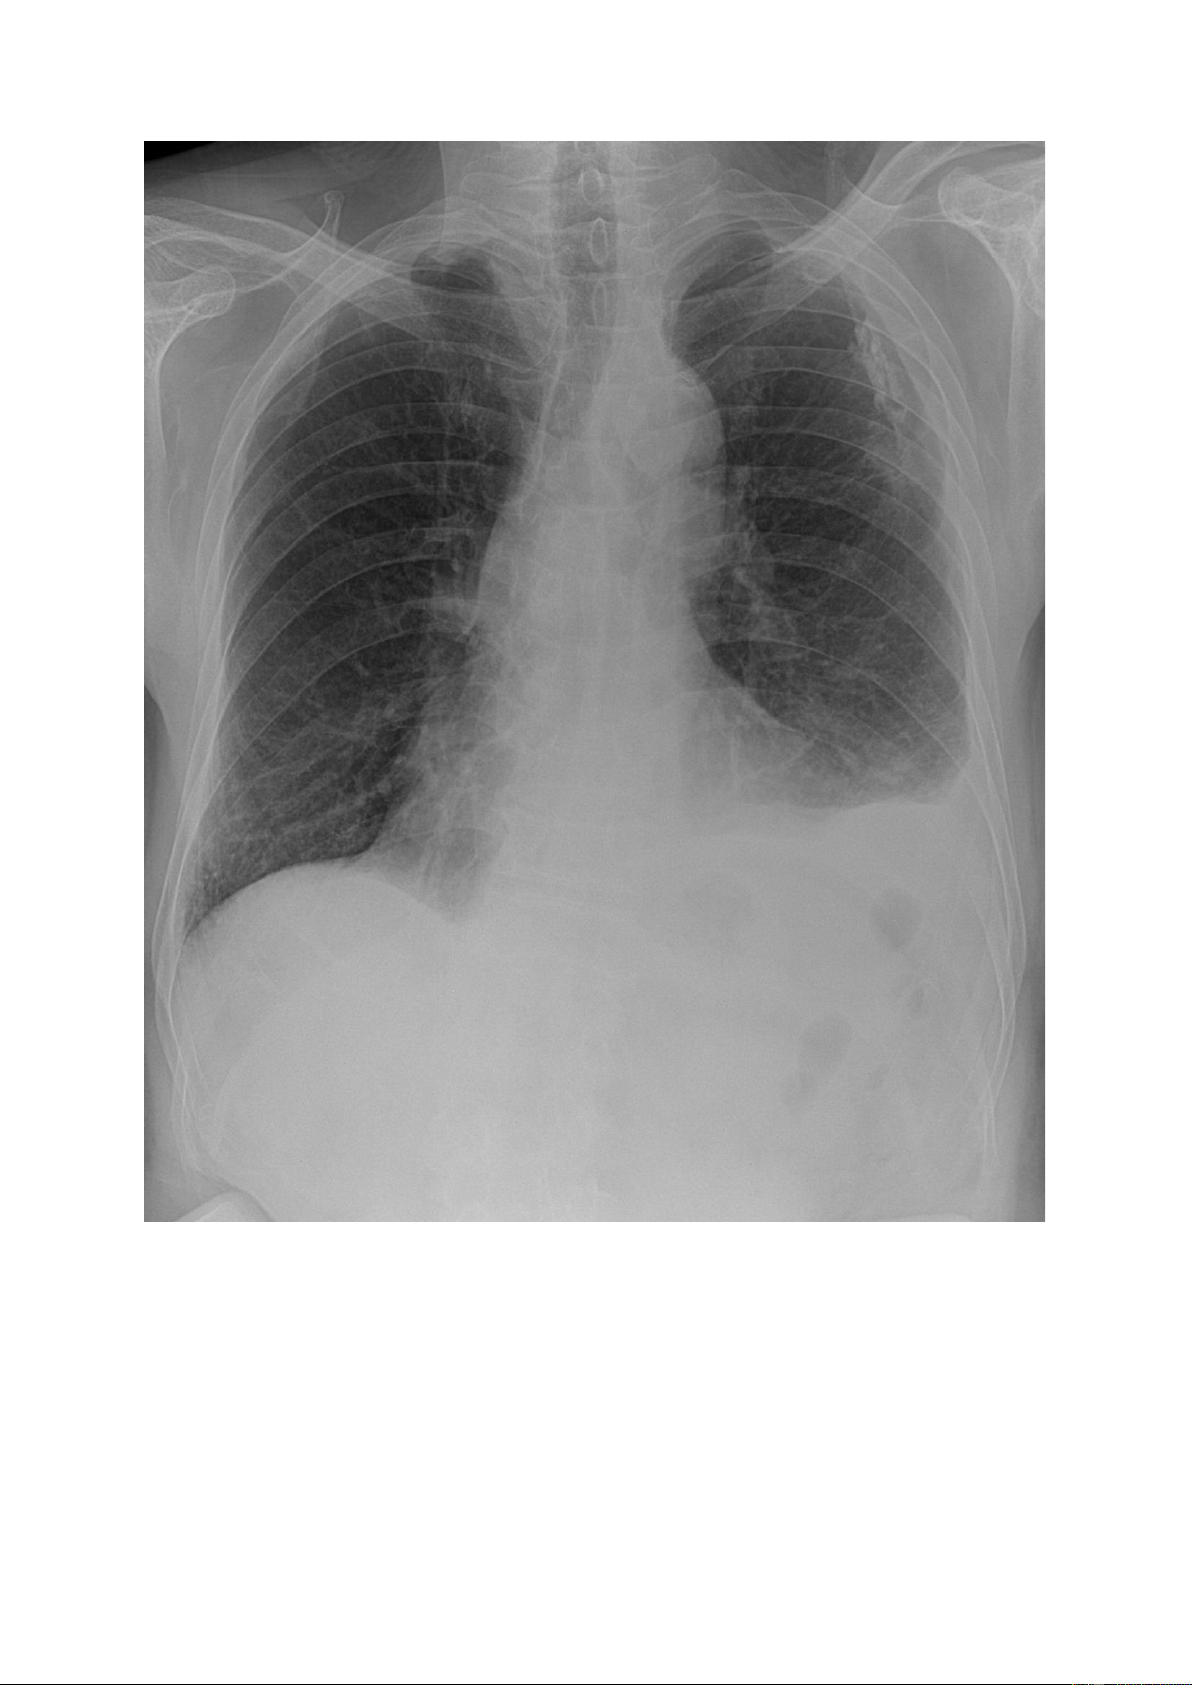

Khối mờ: là tổn thương có kích thước ≥ 3cm; số lượng có thể đơn độc có thể

nhiều. Nếu số lượng nhiều sẽ thấy các khối kích thước đều hoặc không đều nhau, đậm độ cản quang khác nhau. lOMoAR cPSD| 22014077 lOMoAR cPSD| 22014077 1.4.